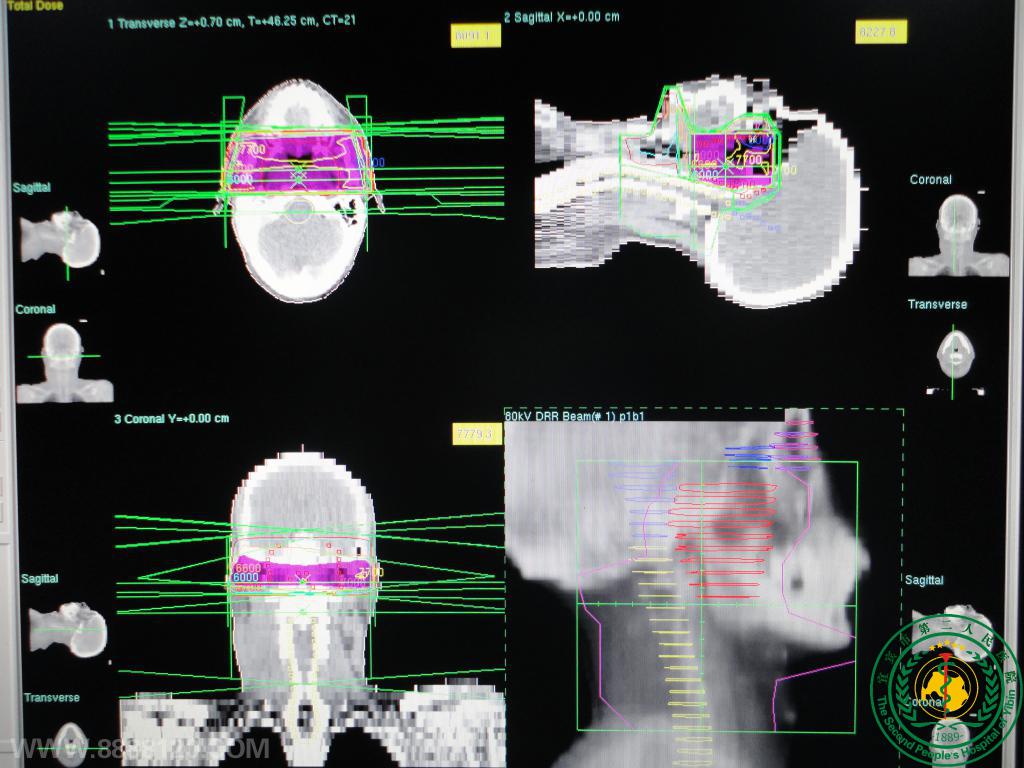

放疗科特色技术

放疗科特色技术3591